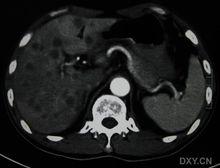

B超:肝內單發或多髮結節,可為低回聲、強回聲或不均勻回聲,腫塊內部回聲為高回聲,周圍包繞寬0.5~1cm的低回聲聲暈,偶爾有的高回聲中央可有少許低回聲區或無回聲區,為癌腫中心出血、壞死所致,此即為“牛眼征”,或稱“靶環征”。CT增強示:腫瘤強化,境界清楚,中央密度多低於周圍部,腫瘤邊緣可顯示環形不規則強化,部分可見“牛眼征”,表現為病灶中心為低密度,邊緣為高密度強化,最外層密度又低於肝實質。

該徵象被認為是轉移性肝癌典型影像表現,可見於任何轉移型肝癌,但多見於腺癌的肝轉移。

CT“牛眼征”